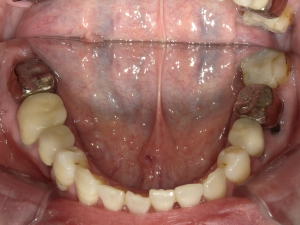

50代 インプラント治療(右上3左上3のみGBR)

| 年代・性別 | 50代・男性 |

| 主訴 | 入れ歯が合わず毎日ヨーグルトしか食べることができないので、しっかり咬めるインプラントにしたい。 |

| 部位 | 右下⑦⑥5④ 上顎③2①①2③ 左下67 |

| 治療期間 | 約9ヶ月 |

| 費用 | ¥4,273,500(税込) |